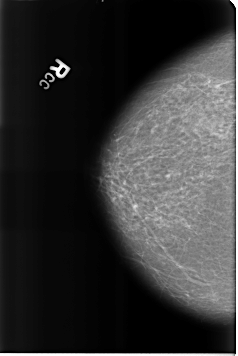

Digital Database for Screening Mammography

Volume: benign_01 Case: B-3159-1

B_3159_1.RIGHT_CC

RIGHT_CC LINES 4616 PIXELS_PER_LINE 3088 BITS_PER_PIXEL 12 RESOLUTION 50 NON_OVERLAY